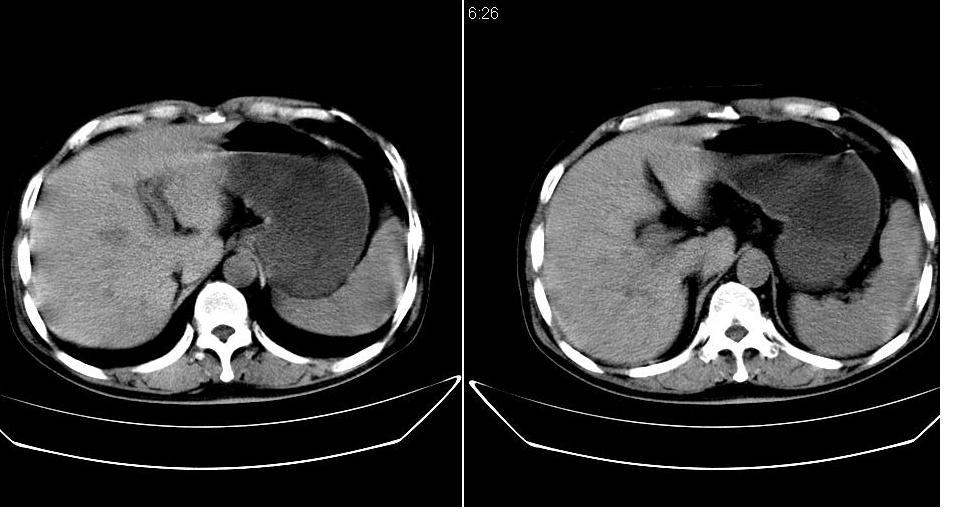

男 48岁,09年8月份在上级医院确诊胰头癌,准备在我院化疗。

胰头体积增大内见低密度影考虑为占位,肿瘤性病变可能性大。

胰头体积增大,外形不规则,密度欠均,支持胰头癌可能性大。